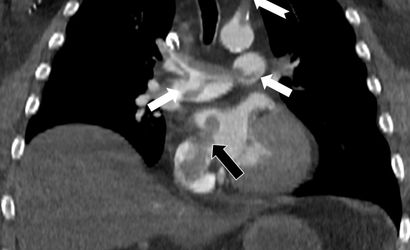

Çalışmada bilgisayarlı tomografi anjiyografisi görüntüleri, toplar damarlardan kaynaklanan pıhtının akciğer damarlarını tıkadığını ortaya koyarken; aynı zamanda kalp odacıkları arasındaki bir delikten geçen pıhtının kalbin sağ tarafından soluna geçip ana atardamara ulaştığını ve sol kol damarını tıkadığı gösterildi.